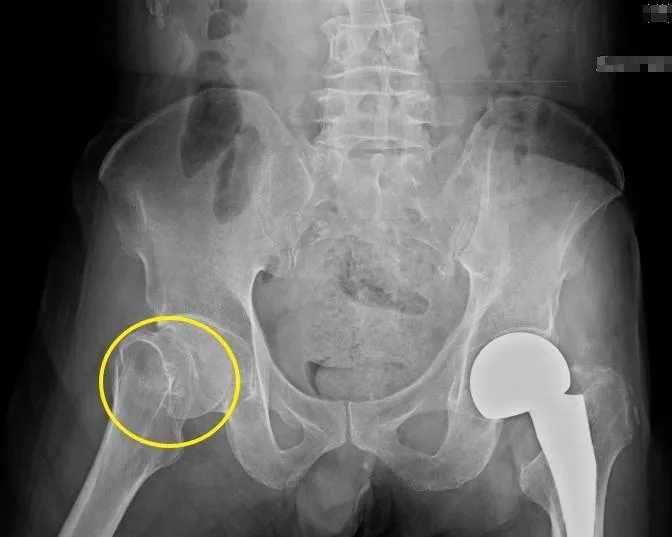

髖部

人工髖關節置換手術

股骨頸骨折

骨盆X光